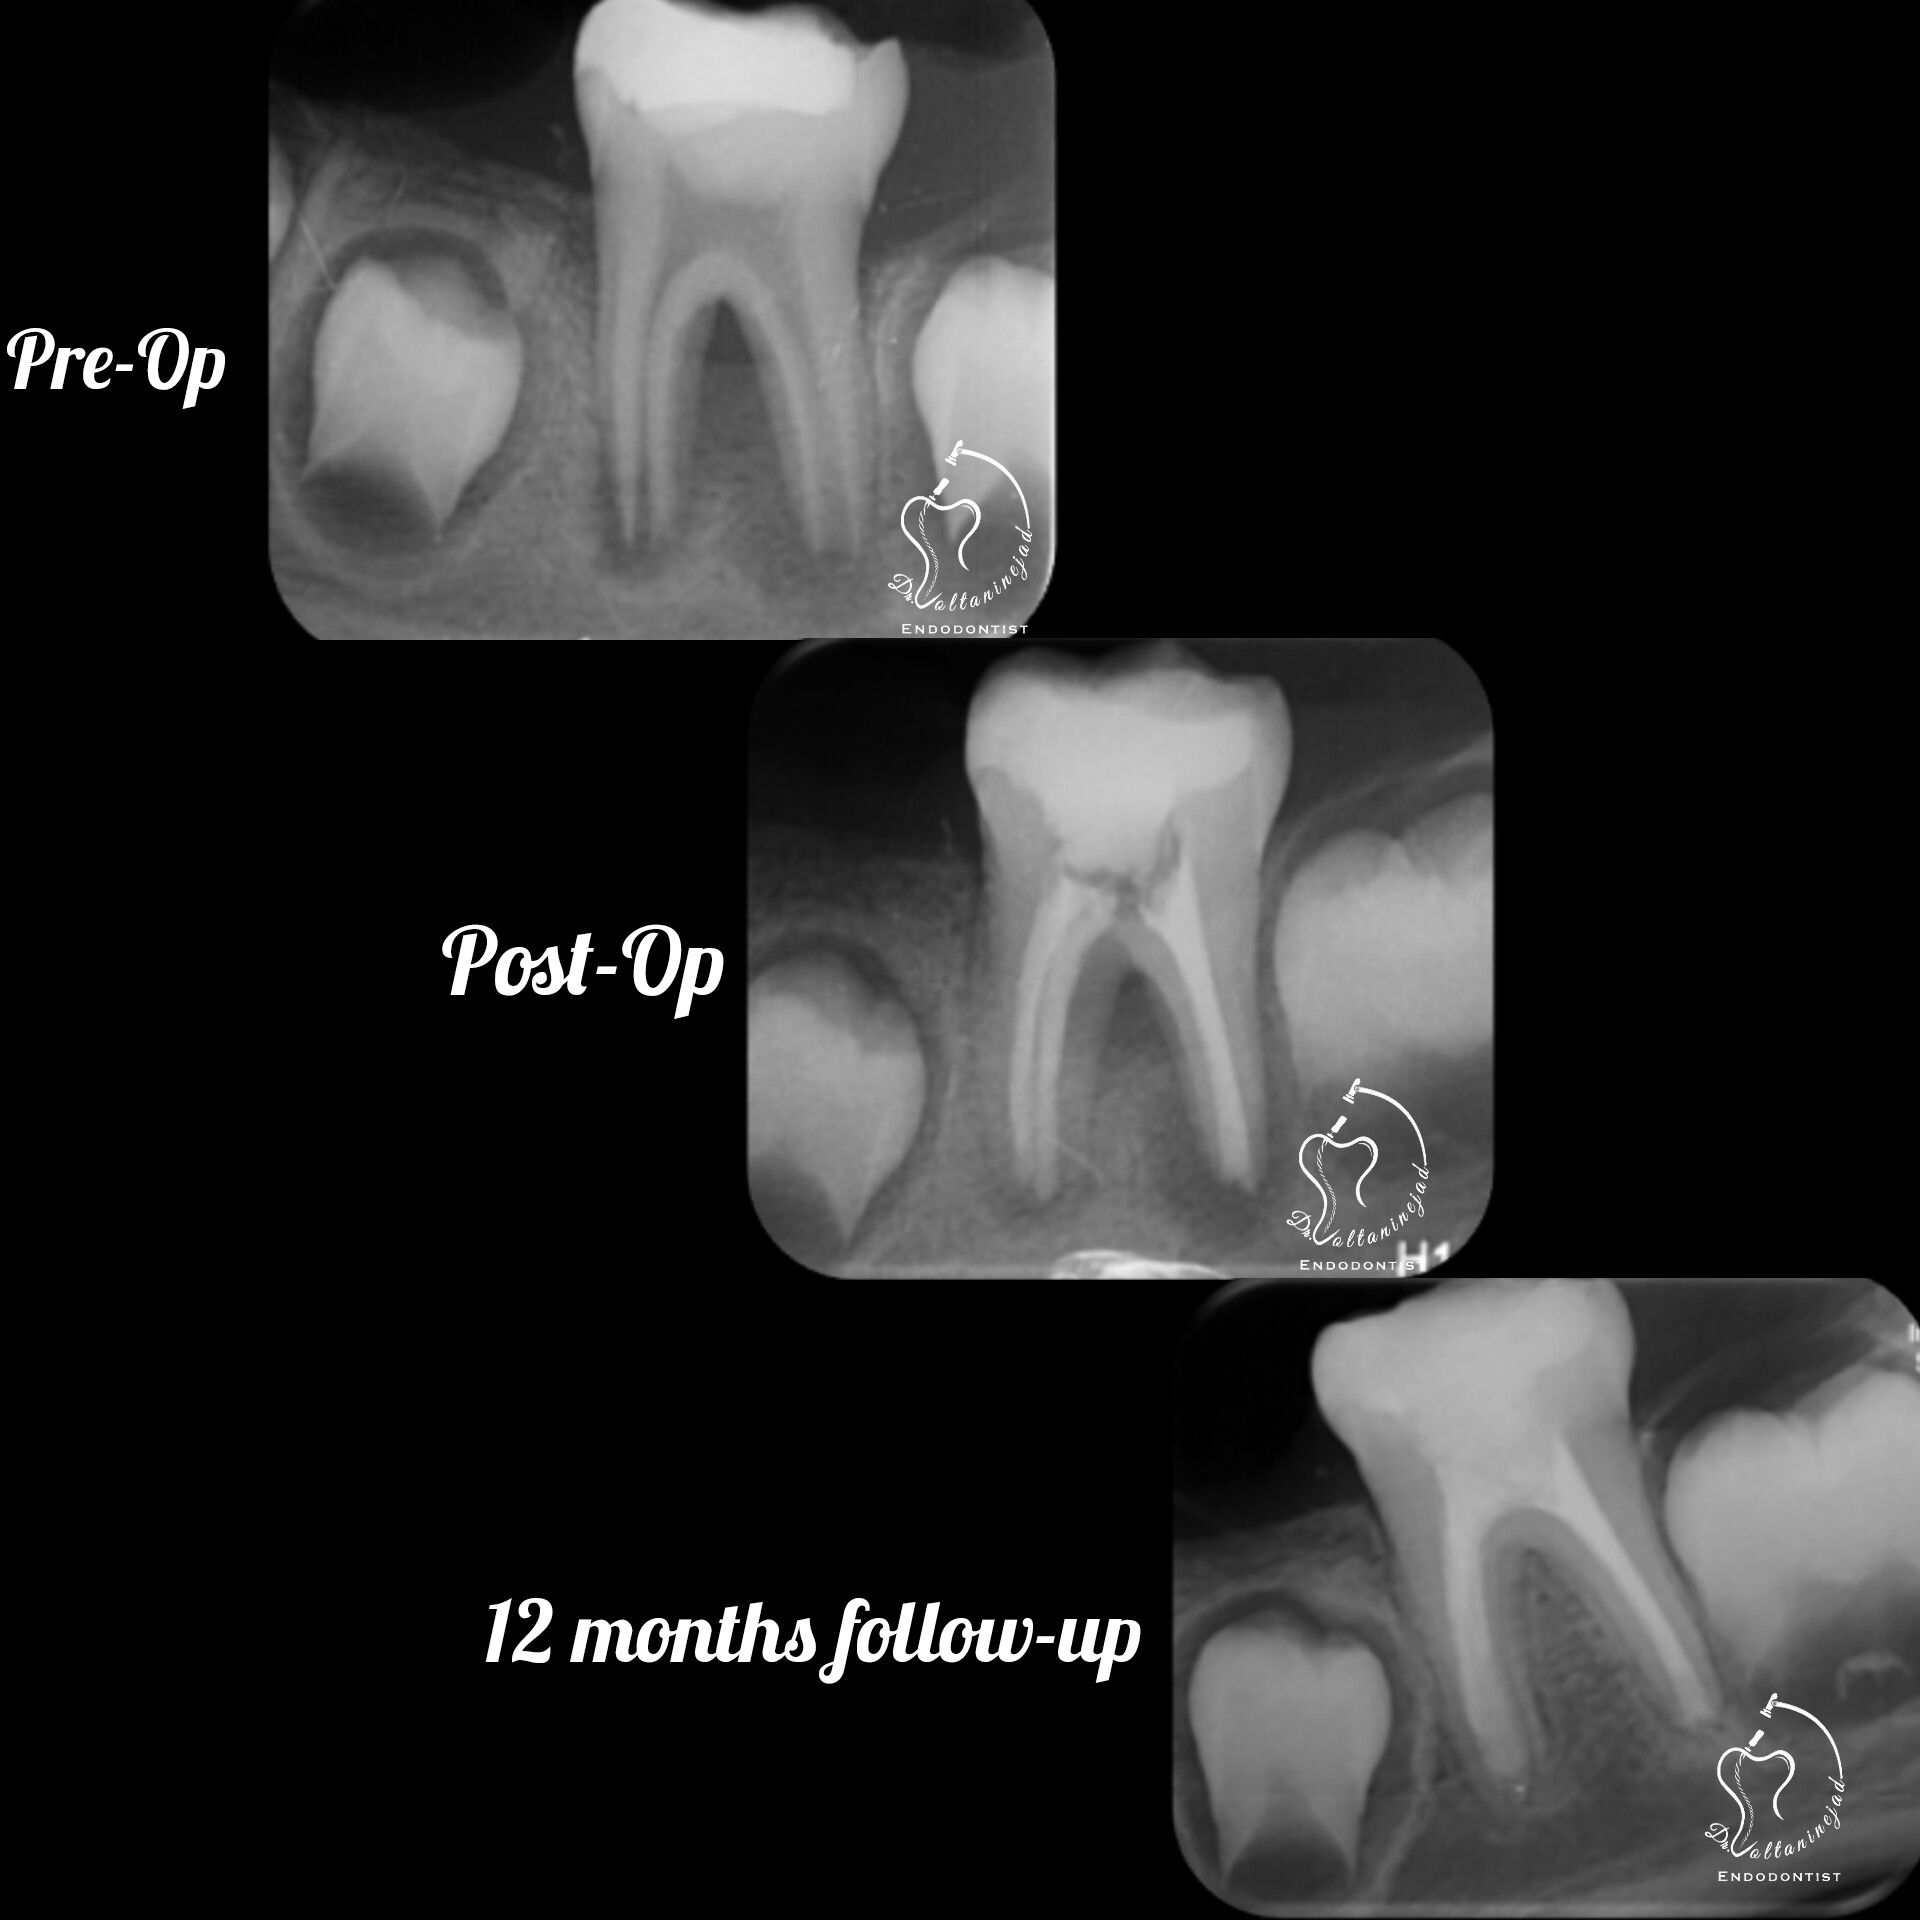

🔹 درمان ریشه دندان با آناتومی نادر

• شرح کوتاه: بیمار ارجاعی با دندان دارای آنومالی (Gemination / دندان دوتایی) که درمان ریشه تخصصی میکروسکوپی با موفقیت انجام شد.

• نتیجه: رفع درد و حفظ دندان به مدت طولانی.